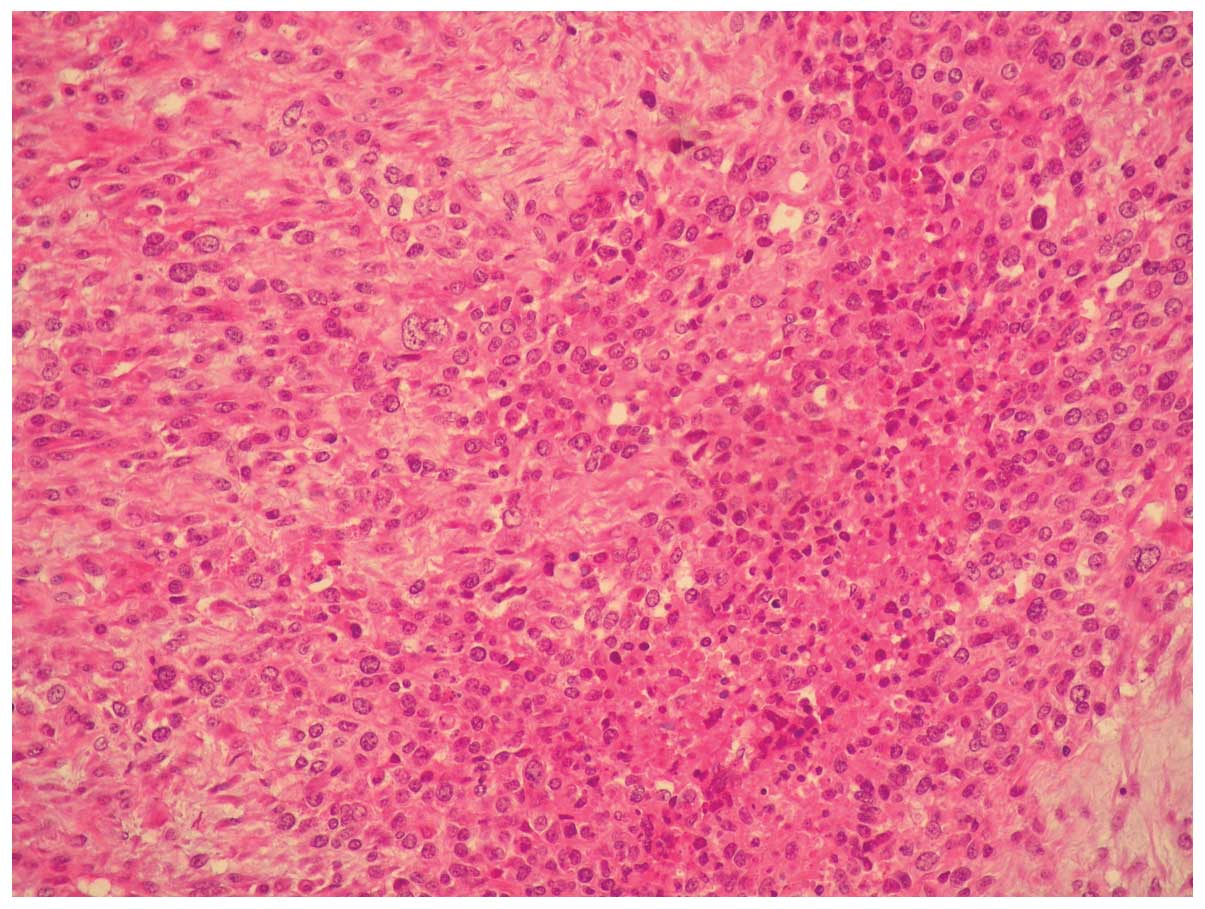

Microscopically, the tumor was composed of moderately

differentiated adenocarcinoma and poorly differentiated sarcoma

with a high mitotic index and necrotic areas (Figs. 1 and 2).